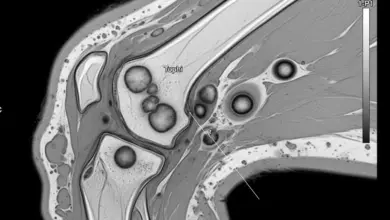

O principal exame para diagnosticar a redução do espaço articular femorotibial medial é a radiografia, especialmente em posição de carga (quando o paciente está em pé).

Esse exame permite visualizar a distância entre os ossos e a presença de outros sinais de artrose, como:

- Osteófitos: Pequenos crescimentos ósseos nas bordas da articulação, conhecidos como “bicos de papagaio”.

- Esclerose subcondral: Aumento da densidade do osso logo abaixo da cartilagem.

- Cistos ósseos: Pequenas cavidades dentro do osso, causadas pelo desgaste progressivo.

Em alguns casos, a ressonância magnética é necessária para avaliar o estado da cartilagem e dos meniscos de forma mais detalhada.